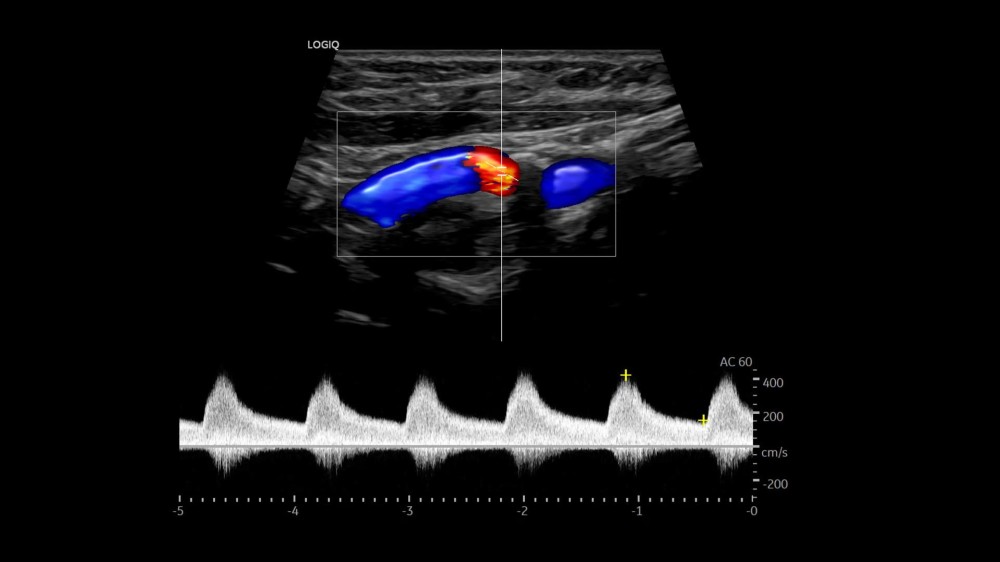

MVI (Micro Vascular Imaging): Kiçik damarların yüksək dəqiqlikli qiymətləndirilməsini təmin edən mikro-damar görüntüləmə rejimi.

Radiantflow™: Kiçik damarların üçölçülü vizuallaşdırılmasını təmin edən texnologiya, MVI ilə birlikdə istifadə edildikdə damar morfologiyasının təhlilini asanlaşdırır.